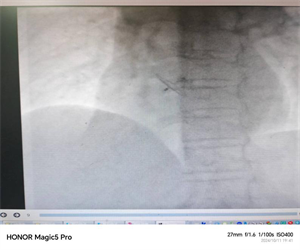

经我院心血管内科充分的病例讨论后,行右心声学造影排查以及经食道心脏超声的进一步证实,终于找到了疾病的“元凶”——卵圆孔未闭。在与患者及家属进行细致的沟通及充分的术前准备。心血管内科介入团队与超声科通力合作,为患者成功进行了卵圆孔未闭介入封堵手术。术后,患者在医护人员的精心照料下恢复良好,现已康复出院。

3.介入治疗:微创介入封堵是经皮导管卵圆孔未闭封堵术,该手术已问世20余年,是成熟的卵圆孔未闭治疗方案,是一种安全、经济的介入治疗手段,用特制的封堵器阻断分流。